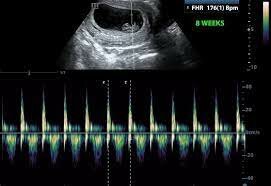

• Period: to

Weeks 7/8

The brain and face begin to grow. The 4 chamber heart- lungs begin to form. Fingers and toes being to form.